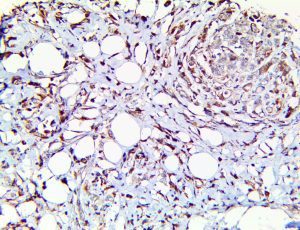

Clinical and laboratory manifestations of HLH include fever, enlarged liver and/or spleen, neurologic dysfunction, coagulopathy, liver dysfunction, cytopenias (i.e., low levels of erythrocytes, leukocytes, and/or platelets), hypertriglyceridemia, hyperferritinemia, hemophagocytosis, and eventually diminished NK cell activity as the immune system becomes progressively paralyzed. HLH can be familial (primary HLH) or secondary to another disease process (sHLH), such as rheumatic disease, in which it is referred to as macrophage activation syndrome (MAS, characterized by elevated ferritin).

This activation induces inflammatory monocytes to highly express IL-6, starting a localized and then systemic cascade effect that results in hyperproduction of IL-6, which accelerates the inflammatory process. Because IL-6 also increases vascular permeability, excessive levels cause blood vessels to become very leaky. This, along with clotting factors released from vascular endothelial cells, stimulates the coagulation cascade, resulting in microthrombosis (tiny clots), which leads to ischemia and tissue death of the kidney, intestines, heart, liver, brain and extremities.